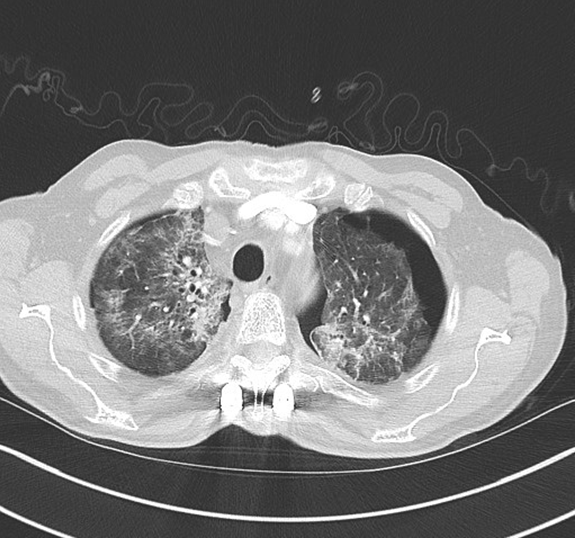

The patient presented to secondary care within eight weeks of completing thoracic radiotherapy complaining of worsening dyspnoea on exertion. On admission blood results showed WCC 6 x109/L, CRP 88 mg/L and Hb 120 g/L. Arterial blood gas analysis confirmed hypoxemic respiratory failure with pH 7.47, PCO2 4.38, PO2 8.5 and HCO3 26.2. CT scan of the thorax demonstrated bilateral small to moderate sized pneumothoraces, bilateral patchy ground glass opacification suggestive of radiation pneumonitis, septal thickening and atelectasis (Figure 1.) The patient was initiated on a tapering course of systemic corticosteroid therapy starting at 60 mg of prednisolone. This led to a rapid improvement clinically, in oxygenation and in chest radiograph appearances Figure 2(A and B). The pneumothoraces were observed closely over time and required no intervention. A chest radiograph performed six weeks post completion of treatment revealed complete re-expansion of both lungs and no evidence of fibrosis.

Figure 2(A and B): Pre-treatment (A) and post-treatment (B) chest radiograph imaging demonstrating resolving pneumonitis eight weeks post steroid initiation.